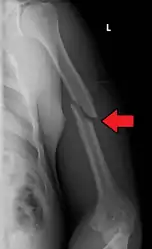

Midshaft humerus fracture with callus formation

Middle

Middle fractures are usually caused by either physical trauma or falls. Physical trauma to the humerus shaft tends to produce transverse fractures whereas falls tend to produce spiral fractures. Metastatic breast cancer may also cause fractures in the humerus shaft.[12] Long spiral fractures of the shaft that are present in children may indicate physical abuse.[5]

Fractures of the humerus shaft are most often uncomplicated, closed fractures that require nothing more than pain medicine and wearing a cast or sling. For midshaft fractures up to 12 weeks may be required for healing.[17]